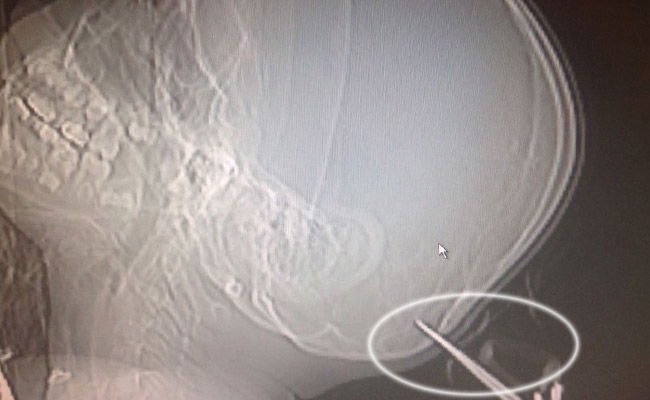

המספריים ננעצו בגולגלתו של הילד כאשר הוא ואחותו היו לבד בביתם, ובמהלך מריבה ביניהם היא זרקה אותן עליו. אחראי מיון ילדים במרכז הרפואי, ד״ר איתמר מונצ׳ק, מסר: ״מצבו של הילד מוגדר בינוני. המספריים חדרו לעצם הגולגולת, אך לאחר בדיקות לא נמצא דימום מוחי. הטיפול בו נמשך בחדר המיון״.

כעת, המספריים שננעצו בעומק של כמה ס״מ הוצאו מראשו, והילד בן השבע הועבר למחלקת כירורגיית ילדים כשמצבו מוגדר יציב.